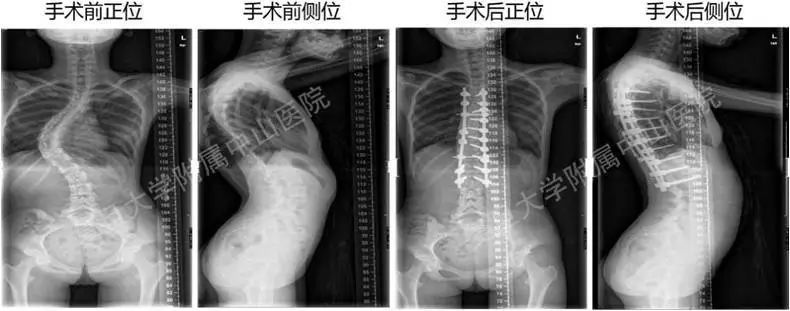

图五 脊柱侧弯的手术治疗

(图片来自复旦大学附属中山医院)

3、手术矫正治疗:仅适用于小部分角度较大(cobb角40°以上)、或者是角度加重较快、保守治疗无效的患者。但是对于先天性脊柱畸形、神经肌肉源性的脊柱畸形,这些患者可能需要脊柱外科医生尽早手术干预,以免出现侧弯相关的心肺功能障碍。前述病例中小李因严重脊柱侧弯(cobb角60°),为避免进行性加重(导致畸形、呼吸或心脏问题),予以手术干预(见图五:小李术前及术后脊柱侧弯矫正情况)。